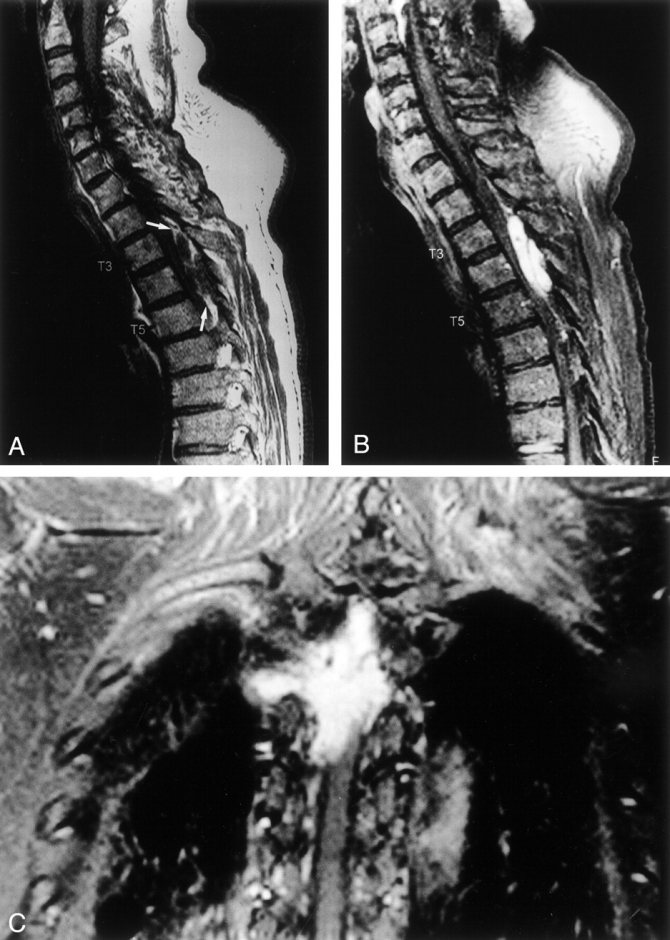

При подозрении на сдавливание опухолью спинного мозга обязательно проводится магнитно-резонансная томография. В ходе обследования выявляется степень повреждения позвонка. При малых размерах опухоли лечение не требуется, но необходимо регулярное наблюдение. Периодический контроль нужен для того, чтобы не пропустить возможный рост новообразования.

Магнитно-резонансная томография – наиболее предпочтительный метод диагностики гемангиолипомы, с ее помощью можно с максимальной точностью, вплоть до миллиметра, определить место локации патологического образования.

Данный метод заключается в помещении пациента в область магнитного поля. Способность молекул человеческого организма менять свой заряд, помогает датчикам прибора сделать снимки поврежденного органа в различных ракурсах и срезах.

МРТ отличает возможность точной визуализации мягких тканей, составляющих гемангиолипому и способность оценить:

- Расположение опухоли относительно позвонка;

- Размеры;

- Вовлеченность тканей, которые ее окружают;

- Состояние сосудов, подходящих к новообразованию;

- Изменения структуры костей.

На основе этих показателей, специалист выберет наиболее предпочтительный метод лечения.